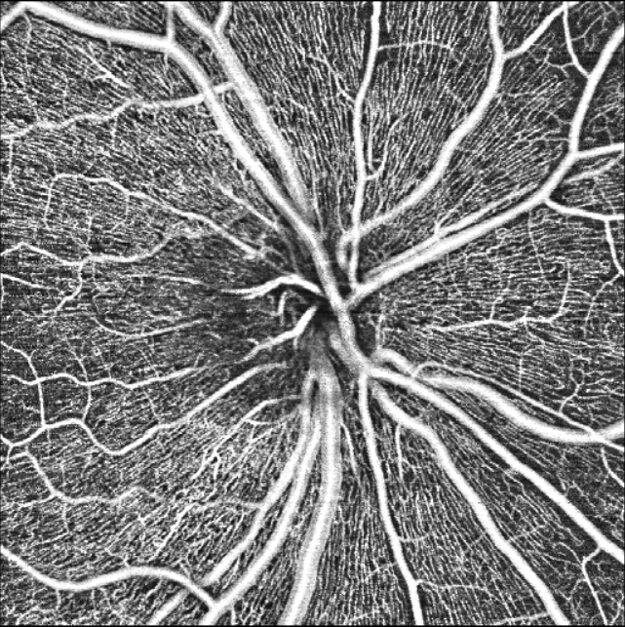

Full Range OCT-A

- 3 x 3 mm, 6 x 6 mm, 12 x 12 mm, 15×15 mm in één opname

- 20 x 20 mm met montage

- Automatische segmentatie in 7 lagen

OCT-A Disc

- 6×6 mm papilscan met OCTA voor bloedstroomanalyse en dichtheidsmeting van bloedvaten in de macula